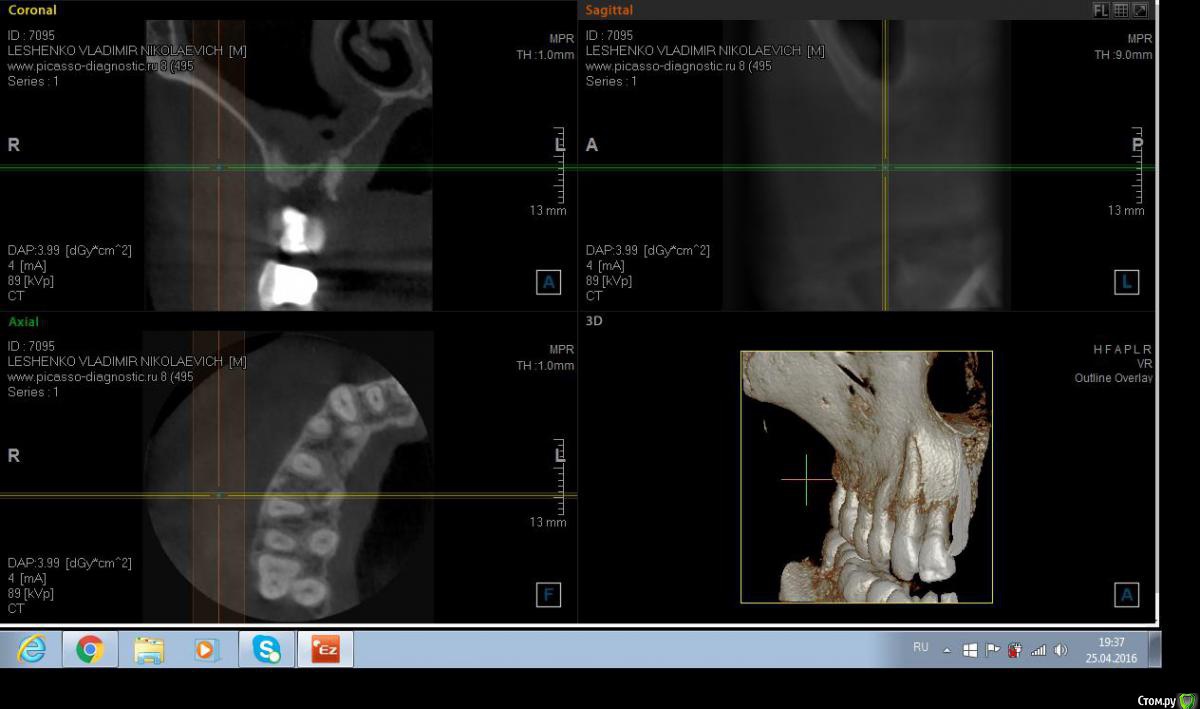

Salma Опубликовано 26 апреля, 2016 Поделиться Опубликовано 26 апреля, 2016 Обратился пациент с болью в области десны в районе 15 и 16 зубов, при осмотре немного отечная десна в области этих зубов, на небе ( не знаю как сказать по другому) между этими же зубами есть щель, с небольшим количеством отделяемого. В общем то промыла , положила метрогил, отправила на кт. Похоже на корень , думаю удалять, но вопросы такие: 1. достаточно ли просто удалить или нужно будет костью присыпать? и что там насчет гайморовой? Ссылка на комментарий

red_butler Опубликовано 26 апреля, 2016 Поделиться Опубликовано 26 апреля, 2016 Да похоже на корень от первого моляра. Просто удалить. Ссылка на комментарий

wladdX Опубликовано 26 апреля, 2016 Поделиться Опубликовано 26 апреля, 2016 Похоже нёбный корень от шестого. Удаляйте. 1 1 Ссылка на комментарий

Salma Опубликовано 26 апреля, 2016 Автор Поделиться Опубликовано 26 апреля, 2016 спасибо ответившим, я думаю что скорее молочный, так как шестерка у пациента есть Ссылка на комментарий

red_butler Опубликовано 26 апреля, 2016 Поделиться Опубликовано 26 апреля, 2016 спасибо ответившим, я думаю что скорее молочный, так как шестерка у пациента естьа восьмой есть? Судя по наклону и расстоянию до премоляра, похоже что все таки от шестерки. Ссылка на комментарий